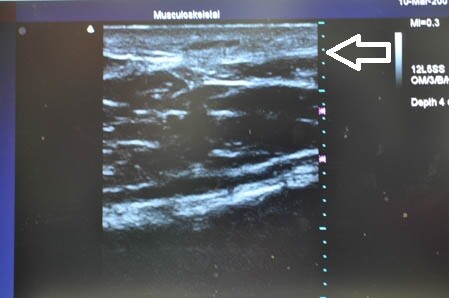

さて今回は3Dタッチビュー(=超音波)

を用いて皮下脂肪層の状態を

適宜チェックしながらの手術になりました。

上腹部の皮下脂肪の状態を

手術直前と直後で比較して見てみましょう。